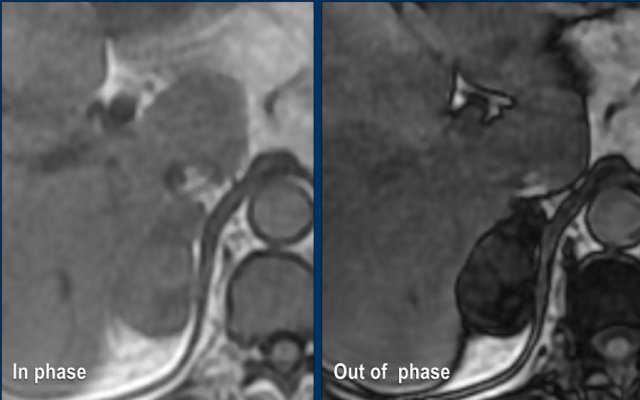

MRI Out-of-phase imaging

Lipid-poor adenomas can also be diagnosed with out-of-phase imaging.

They contain enough microscopic fat to cause a signal drop on out-of-phase imaging compared to in-phase imaging due to the chemical shift artefact.

These images are of a 65- year-old female patient with an incidental discovery of a right adrenal mass on an abdominal ultrasound performed for renal stones.

The presence of microscopic fat is demonstrated by the signal drop on the opposed-phase image.

The patient was followed for 2 years, because the lesion is slightly inhomogeneous and measures 5.2 cm.

The lesion did not change in size and was not hormonally active.

It was diagnosed as a lipid-poor adenoma.

MRI performed for a left adrenal incidentaloma discovered on a non-contrast and arterial phase CT scan in a 61-year old male patient with an abdominal aneurysm.

On the non-contrast CT density was 18 HU.

T1 out-of phase image shows subtle inhomogeneous signal drop compared to in-phase.

Note that the fat-suppressed T1 does not help in the detection of microscopic intracellular fat.